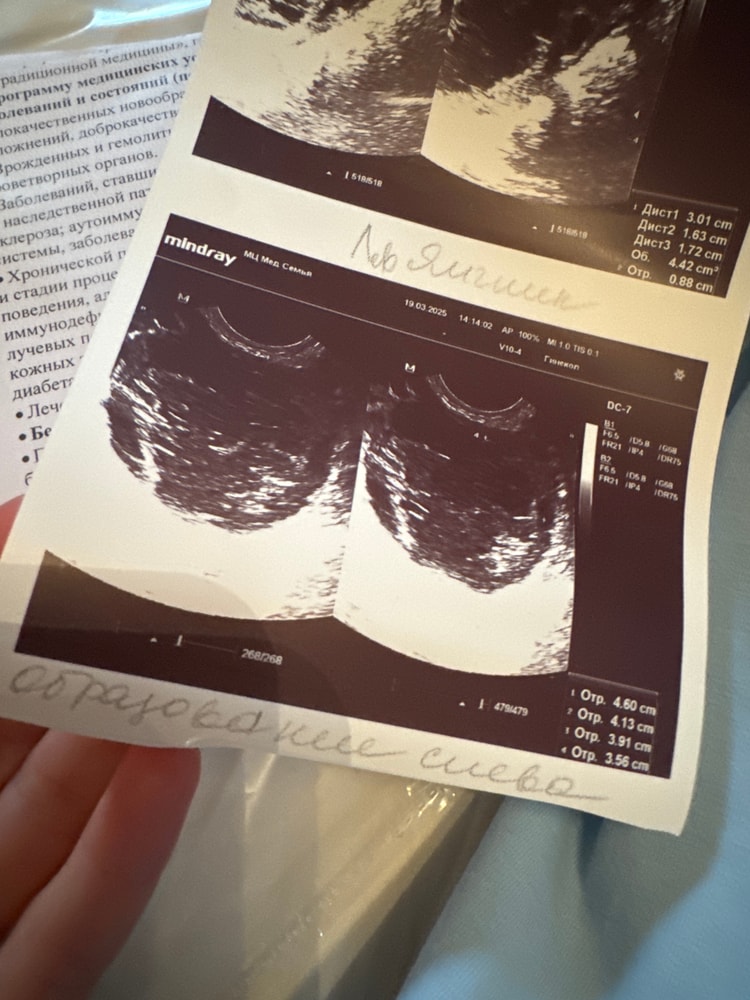

Гинекологические заболеванияНашли кисту около яичника 4,5 см !!! Это очень много да ???🥹😢😭